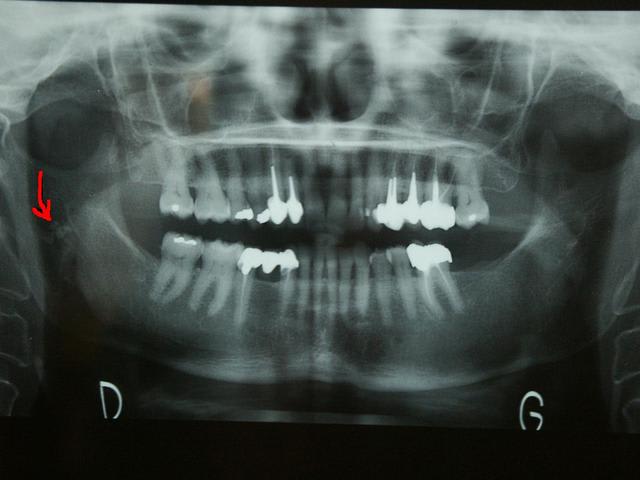

Bonjour

Que peuvent etre ces images de calcification ?

Cela me semble un peu bas pour la parotide et un peu haut pour la sous-max

... artério-sclérose carotidienne?

Je pensais aussi à ca : faut il l'adresser a son cardio ?